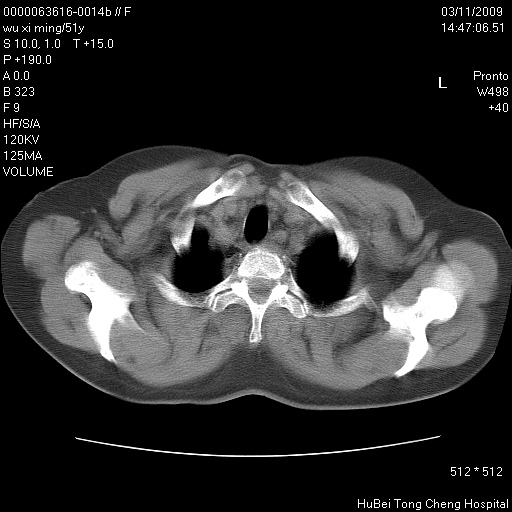

患者 女,51岁。因“胆囊炎,胆囊结石”,行常规术前胸部x线检查发现:右上肺结节病灶,建议行进一步检查。患者无咳嗽、咳痰及咯血等呼吸道症状,近期出现背部疼痛不适。

胸部ct轴位平扫(层厚10mm,螺距1.5,重建间隔10mm;部分层面:层厚3mm,螺距1.0,重建间隔3mm),图像如下: